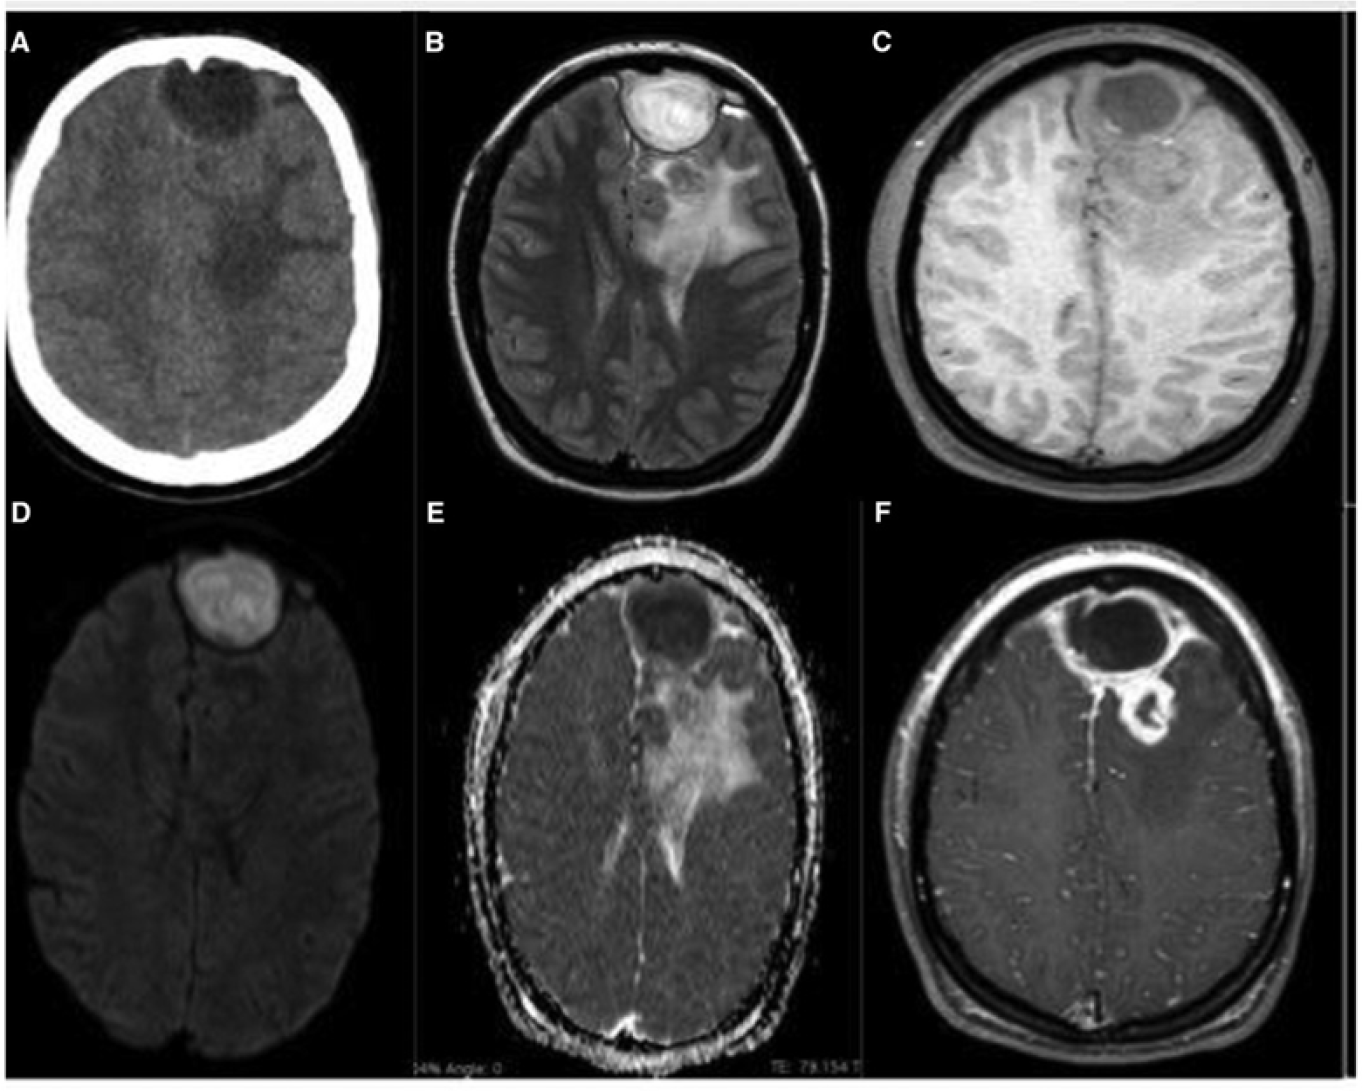

Because of the risk of intracranial extension and the potentially nonspecific symptoms that could accompany empyema formation, abscess development, or cerebritis, practitioners should maintain a high index of suspicion for central nervous system complications. With this in mind, practitioners should obtain three-dimensional imaging for any patients presenting with fever, headache, and forehead swelling or ear proptosis. Contrast is essential for identifying rim-enhancing abscesses or empyemas. Computed tomography generally is favored in the initial characterization of mastoiditis (because of the better definition it provides when evaluating the structures of the temporal bone), while magnetic resonance imaging is preferable for identifying intracranial empyema and abscess formation. (See Figures 5 and 6.)

Figure 6. Early Rocky Mountain Spotted Fever on Arm |

![]() |

Source: Centers for Disease Control and Prevention. Rocky Mountain spotted fever (RMSF): Signs and symptoms. Last reviewed Feb. 19, 2019. https://www.cdc.gov/rmsf/healthcare-providers/signs-symptoms.html |